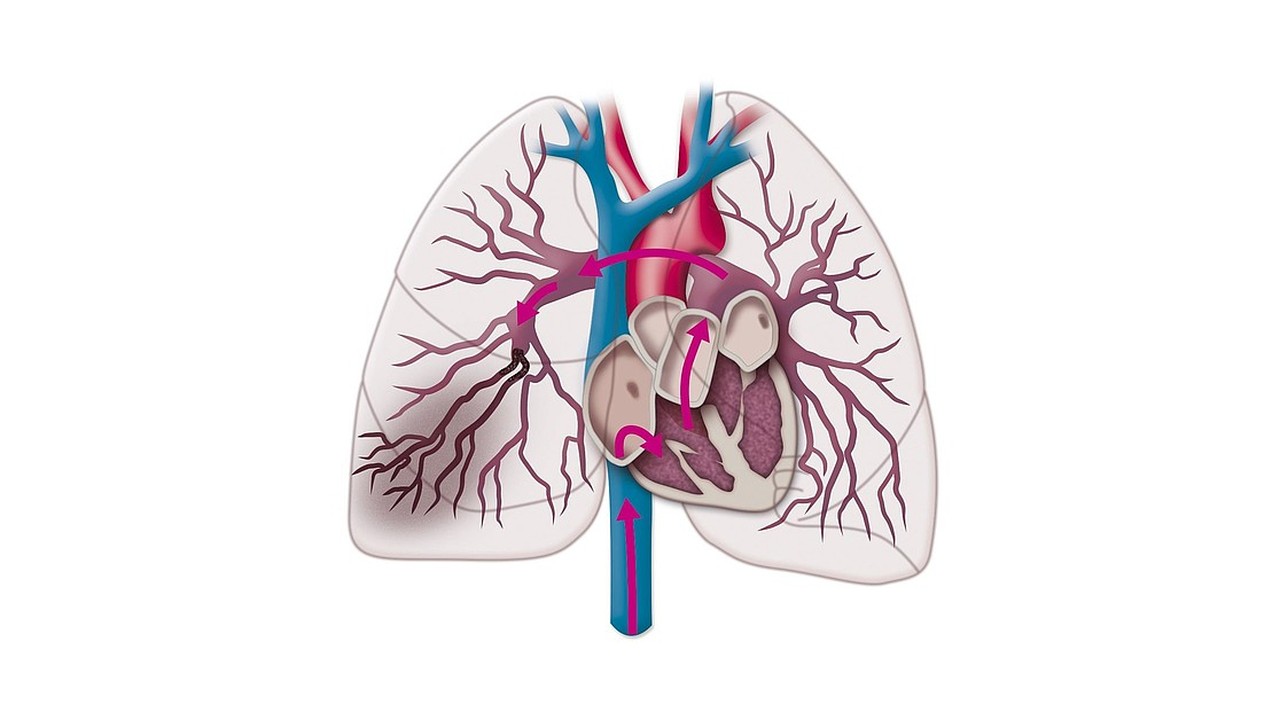

Nguyên nhân thường gặp nhất của nhồi máu phổi là thuyên tắc phổi.

Một số nguyên nhân hiếm gặp khác có thể gây ra nhồi máu phổi. Chúng bao gồm ung thư, các bệnh tự miễn dịch như lupus, các bệnh nhiễm trùng khác nhau, bệnh hồng cầu hình liềm, bệnh phổi thâm nhiễm như bệnh amyloidosis, thuyên tắc khí,...

Nguyên nhân phổ biến nhất gây nhồi máu phổi là do thuyên tắc phổi.